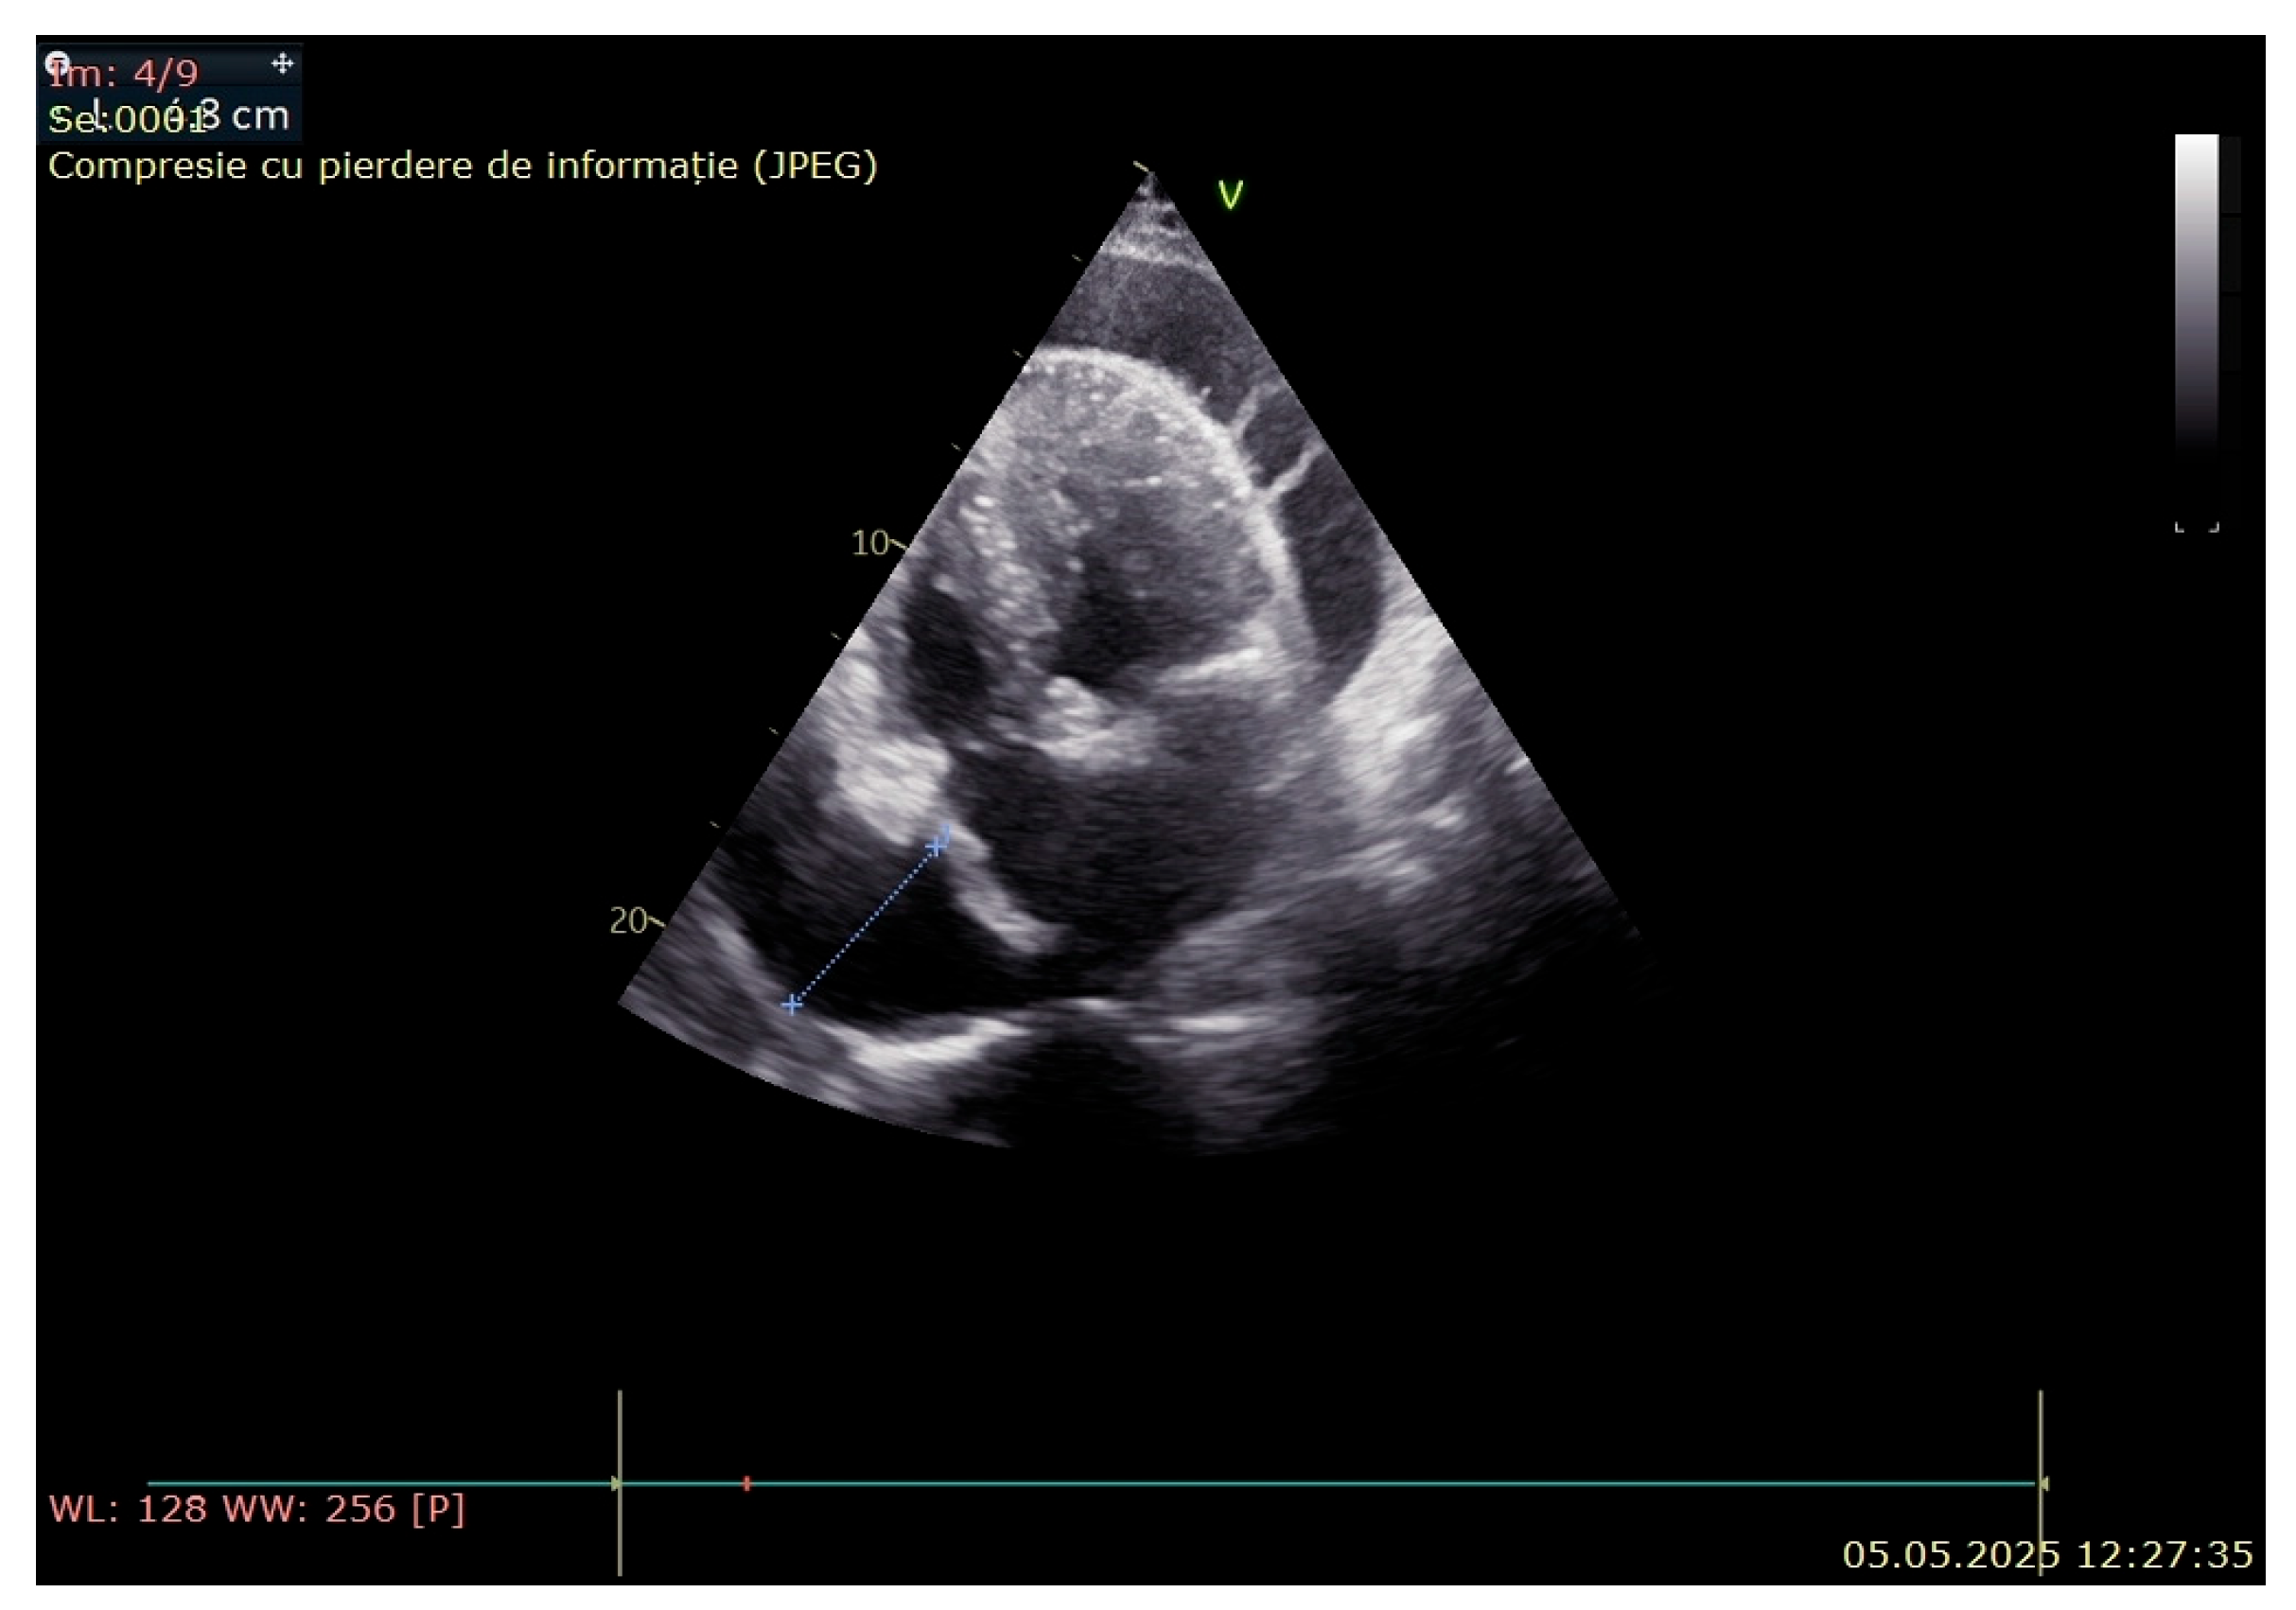

3. Case Presentation